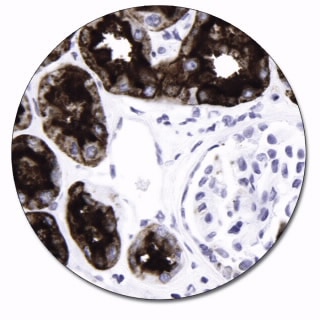

Reacts with a carbohydrate antigen, termed Lewis X (Lex), X hapten or CD15 antigen, expressed on Reed-Sternberg cells and various other cell types including myeloid cells and epithelial cells. Results aid in the classification of acute myeloid leukemia and chronic myelogenous leukemia, as well as carcinomas derived from various organs (1). The antibody is of value in the identification of Reed-Sternberg cells for classification of Hodgkin's lymphoma.